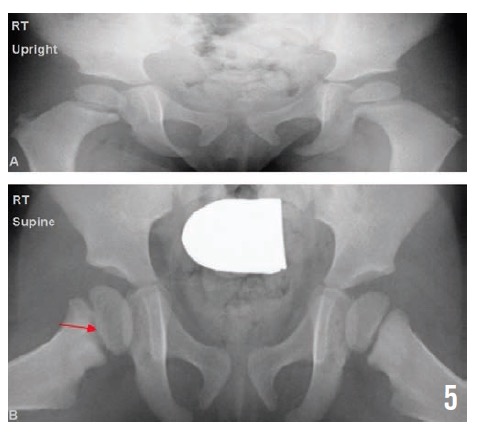

Radiographs of the pelvis at 2, 4, and 10 months (Figures 3, 4, and 5, respectively) showed healing osteomyelitis of the proximal right femur and changes that were concerning for early physeal closure at the right hip joint. Continued radiographic follow-up was suggested at that time.